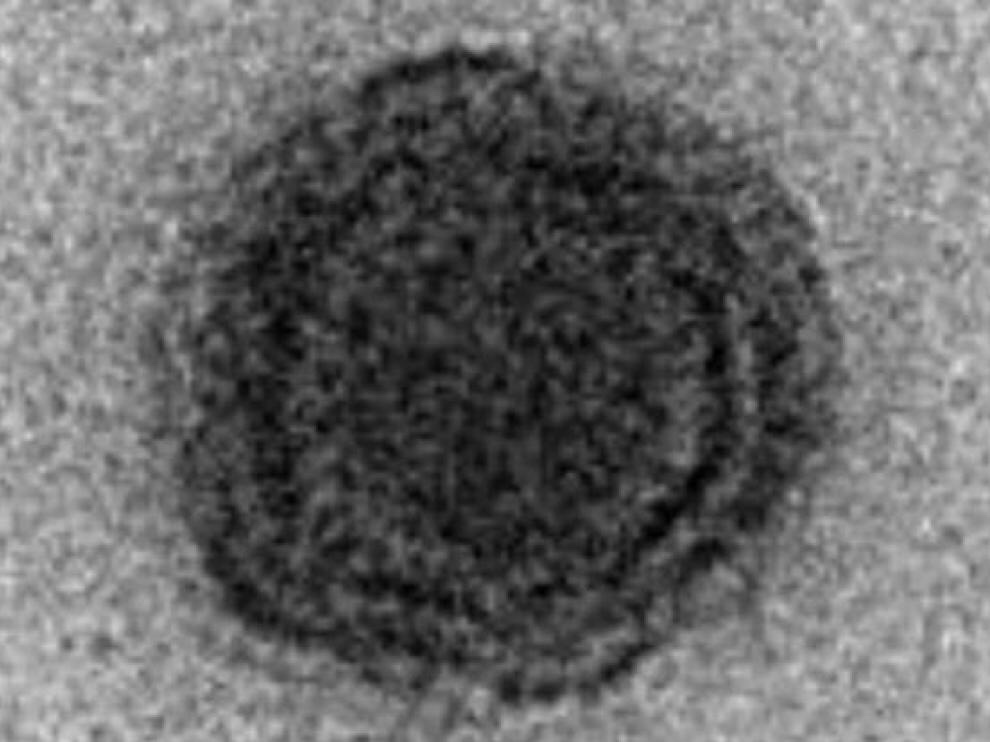

Los científicos no fueron capaces de identificar el 90% de los genes del nuevo virus Un equipo de científicos ha identificado un nuevo y «misterioso» tipo de virus que los ha dejado desconcertados. Hasta el 90% de sus genes no se habían visto nunca […]